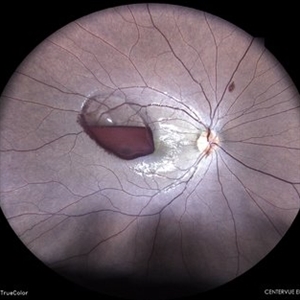

Old Supero-Temporal Branch Retinal Vein Occlusion with Macular Hole Right Eye Fundus

May 23 2021 by Akansha Sharma

Fundus photograph of a 36-year-old female presented with supero-temporal branch retinal vein occlusion with macular hole in right eye.

Photographer: Dr. Akansha Sharma-Retina Foundation

Condition/keywords: branch retinal vein occlusion (BRVO), macular hole